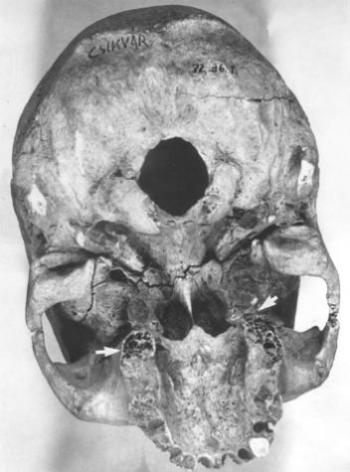

84. ábra. Alveolitis, gennyes csontgyulladás nyomai valamennyi fog körül (nyíl)

A fogkövek vizsgálatát ritkán végzik, mindössze néhány tudósítás olvasható, noha a szájüreg flórájára, a táplálék minőségére, olykor a konyhatechnikára is felvilágosítást szolgáltathat. Dr. Török Katalin fogorvossal közösen végeztük el 20 váci múmia (30-68 év közöttiek) fogköveinek mikroszkópos elemzését. Valamennyiben kimutathatók Gram pozitív és negatív pálcák, Gram pozitív coccusok, de sohasem találtunk Gram negatív coccust. Három alkalommal gombatelepek illetve gombaspórák látszottak (85. ábra, 86. ábra, 87. ábra). Ez arra utal, hogy az idők folyamán jelentősen megváltozott az emberi szájflóra, ugyanis a neandervölgyi ember fogkövében csak pálca alakú baktériumokat (Pap és mtsai 1995 és 1996), egy ősindián temető anyagában viszont kizárólag coccusokat találtak (Magennis és Cummings 1996), a recens fogkövek mikroba összetétele fajgazdagabb (Silvestrini és mtsai 1992). A 18–19. században jelenhettek meg a gombák a szájüregben (10. táblázat). Roberts és Woodward (1996) két angliai temető leletein a fogkövek ételmaradványait tanulmányozva azt állítják, hogy nem lehetett lényeges különbség a lepratelep lakóinak és a telepen kívül élőknek a táplálkozása között. Magennis és mtsa (1996) mexikói ősindián populáció fogköveiben kukorica-keményítő szemcséket, perjefű-félék maradványait, fitolithokat azonosítottak. Valamennyi esetünkben növényi rostok, kristályok és fitolithok (90. ábra), kétharmadukban búza-, kukorica-, burgonyakeményítő szemcsék (89. ábra) fordultak elő, de rizskeményítővel sohasem találkoztunk. A 18–19. században mind a kukorica, mind a burgonya fontos néptáplálék lehetett. A fogkőbe zárt kollagénrostrészletek hőkárosodást mutattak, jelezvén, hogy nem nyers (kolbász, füstölt sonka, szalonna), hanem hőkezelt (sütött, vagy főzött) ételből származnak. Izomrostokat két alkalommal találtunk, számos képletet nem tudtunk azonosítani (85. ábra, 86. ábra, 87. ábra, 88. ábra, 89. ábra, 90. ábra).